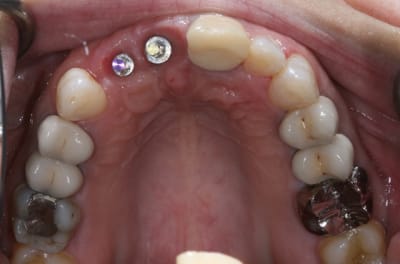

Bon ben j'ai implanté avant d'avoir refait la 21. Du coup j'ai mésialé la pose de 11 pour compenser la distalisation de 21.

Au final je n'ai pas fait de greffe osseuse... et j'ai réalisé une technique de rouleau sur 11-12 mais je reste un peu court à mon goût.

J'ai mis en place des transitoires sur 11-12-21 pour temporiser 3 mois pour voir la maturation des tissus mous.

Je réaliserai dans un second temps des piliers procera.

Je mets quelques photos de la patiente au cab et du prothèsiste d'Epinal.

La vraie difficulté a été de retrouver le milieu incisif pour déterminer la position des implants.